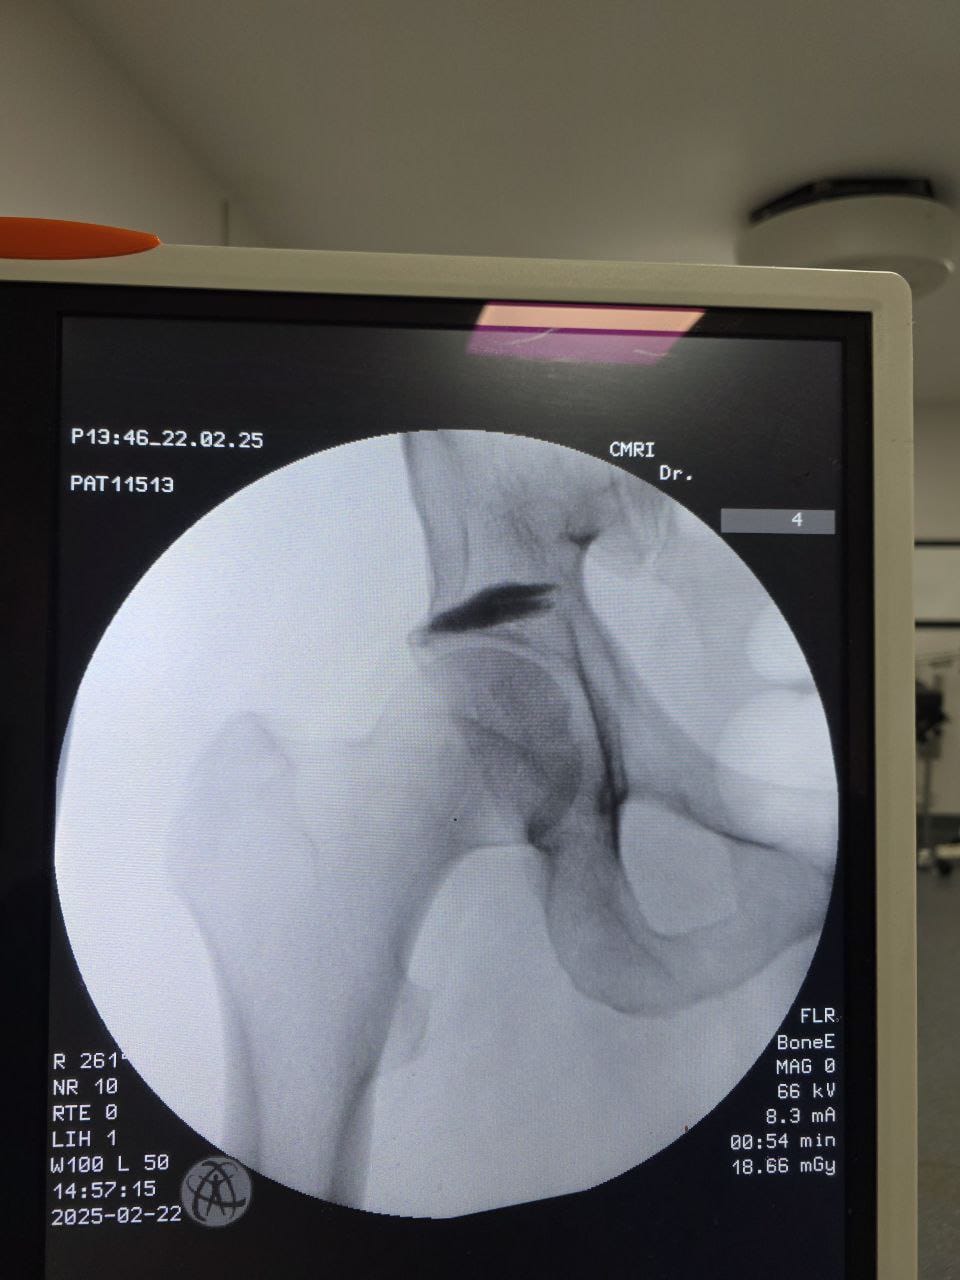

Procedures